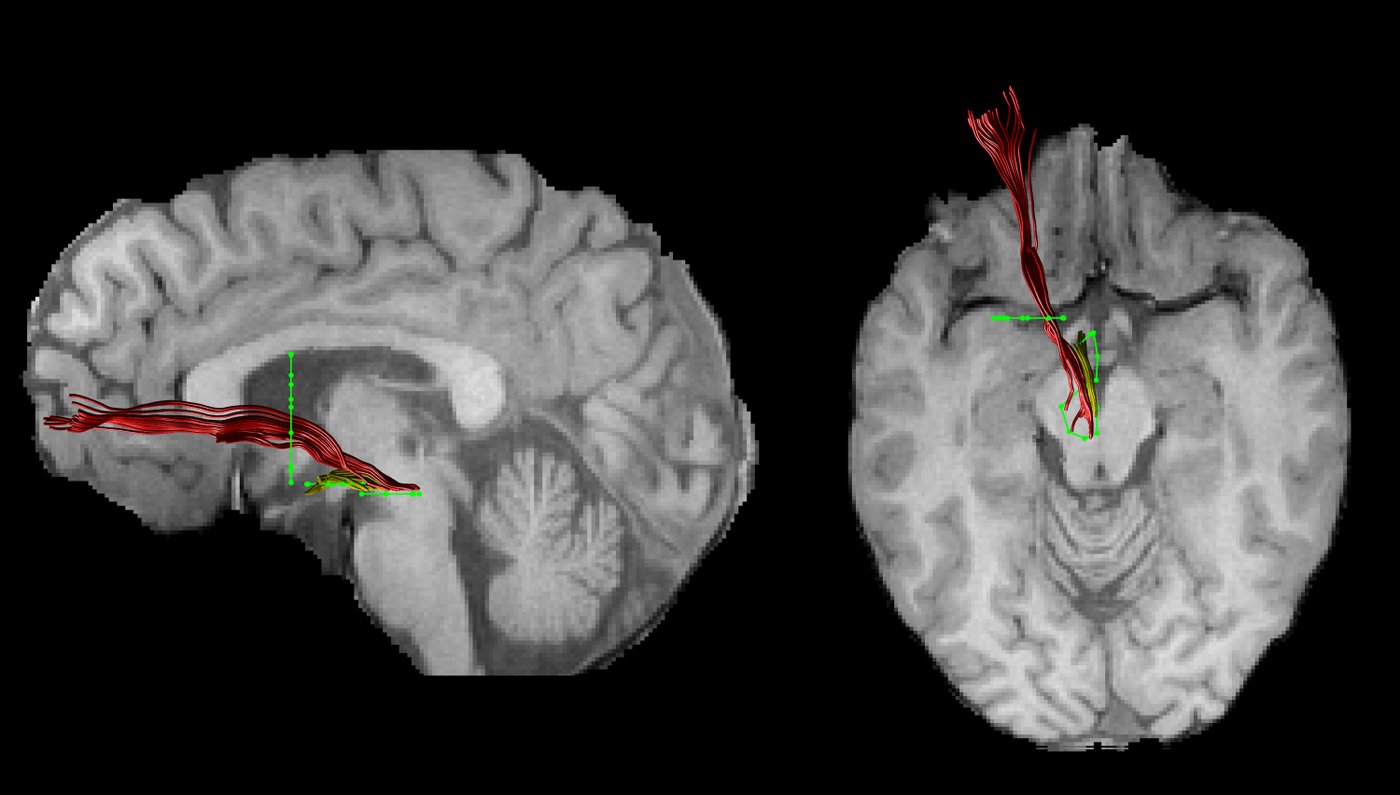

Tract reconstruction

The FA images of each subject were warped to their respective FSPGR image using the linear registration tool FLIRT (Jenkinson et al. Reference Jenkinson, Bannister, Brady and Smith2002). Inverse parameters were applied to transform the FSPGR image to the FA image. Afterwards, FSPGR images were used as a template to draw regions of interest (ROI) for virtual dissection of the different branches of the MFB. Seed regions were drawn by one experimenter (T.B.) who was blind to the diagnosis of participants. For both the imMFB and slMFB a ROI surrounding the VTA was drawn in the horizontal section. Anatomical borders were laterally the substantia nigra, anteriorly the mammillary bodies and posteriorly the red nucleus. For reconstruction of the imMFB a second ROI surrounding the hypothalamus was drawn on a horizontal section one section above the VTA ROI. For reconstruction of the slMFB a second ROI was drawn surrounding caudate and putamen on a coronal section at the height of the NAc. The anatomical course of each tract was carefully checked for each subject (see Fig. 1). Due to the particular interest in the role of the MFB in reward processing, the focus was placed on segments of the MFB dorsal to the VTA including projections from the VTA to NAc, hypothalamus and the OFC, core regions of reward processing (Haber & Knutson, Reference Haber and Knutson2010). Seed regions for the comparison tract (MCP) were drawn on a coronal section, where left and right MCP can be clearly identified. The MCP was chosen because it can be reliably isolated but is not predicted a priori to be affected in RD. Because of the spatial overlap of left and right MCP in regions of the pontine nuclei (Nieuwenhuys et al. Reference Nieuwenhuys, Voogd and van Huijzen2008), the MCP was treated as a sole ROI. Mean FA was derived for each reconstructed tract for each subject. In addition, the average mean diffusion (MD) and the axial and radial diffusivity (AD, RaD) were computed, to facilitate follow-up of any group differences seen in FA, our primary outcome measure.

Fig. 1. An individual example of the two reconstructed branches is shown for the left imMFB (yellow) and the left slMFB (red). Regions of interest are displayed in green.